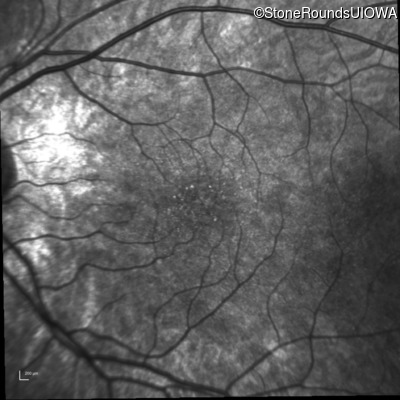

Infrared Fundus Photograph - Left - 10/16 sc

Exemplar